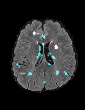

In recent years, data-driven machine learning (ML) methods have revolutionized the computer vision community by providing novel efficient solutions to many unsolved (medical) image analysis problems. However, due to the increasing privacy concerns and data fragmentation on many different sites, existing medical data are not fully utilized, thus limiting the potential of ML. Federated learning (FL) enables multiple parties to collaboratively train a ML model without exchanging local data. However, data heterogeneity (non-IID) among the distributed clients is yet a challenge. To this end, we propose a novel federated method, denoted Federated Disentanglement (FedDis), to disentangle the parameter space into shape and appearance, and only share the shape parameter with the clients. FedDis is based on the assumption that the anatomical structure in brain MRI images is similar across multiple institutions, and sharing the shape knowledge would be beneficial in anomaly detection. In this paper, we leverage healthy brain scans of 623 subjects from multiple sites with real data (OASIS, ADNI) in a privacy-preserving fashion to learn a model of normal anatomy, that allows to segment abnormal structures. We demonstrate a superior performance of FedDis on real pathological databases containing 109 subjects; two publicly available MS Lesions (MSLUB, MSISBI), and an in-house database with MS and Glioblastoma (MSI and GBI). FedDis achieved an average dice performance of 0.38, outperforming the state-of-the-art (SOTA) auto-encoder by 42% and the SOTA federated method by 11%. Further, we illustrate that FedDis learns a shape embedding that is orthogonal to the appearance and consistent under different intensity augmentations.